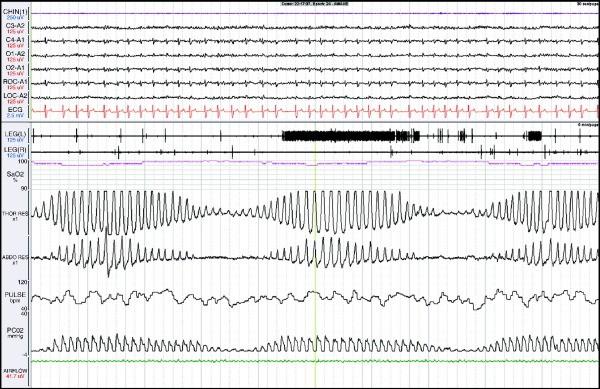

CSR • If there is at least 3 consecutive cycles of cyclical crescendo and decrescendo change in breathing amplitude • + atleast one of the below : 1. 5 or more central apnea / hypopnea per hr of sleep. 2. The cyclic cresendo and decresendo change in breathing amplitude has a duration of atleast 10 consecutive mins. CSR has variable cycle length that is most commonly in the range of 60 seconds.